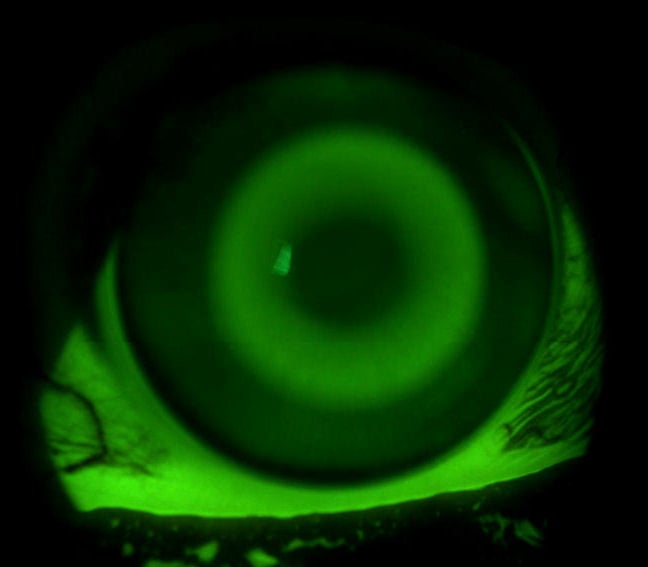

For years the standard optic zone for orthokeratology lenses has been 6.0mm. The OK®-EX uses a variable optic zone diameter that is calculated to provide a consistent tear film depth at the edge of the optic zone. The higher the target power, the smaller the optic zone becomes. Hyper-Aspheric treatment zones create the ultimate flattening power. The OK®-EX also features double aspheric reverse and alignment zones that help center the lens on even the most difficult corneas.